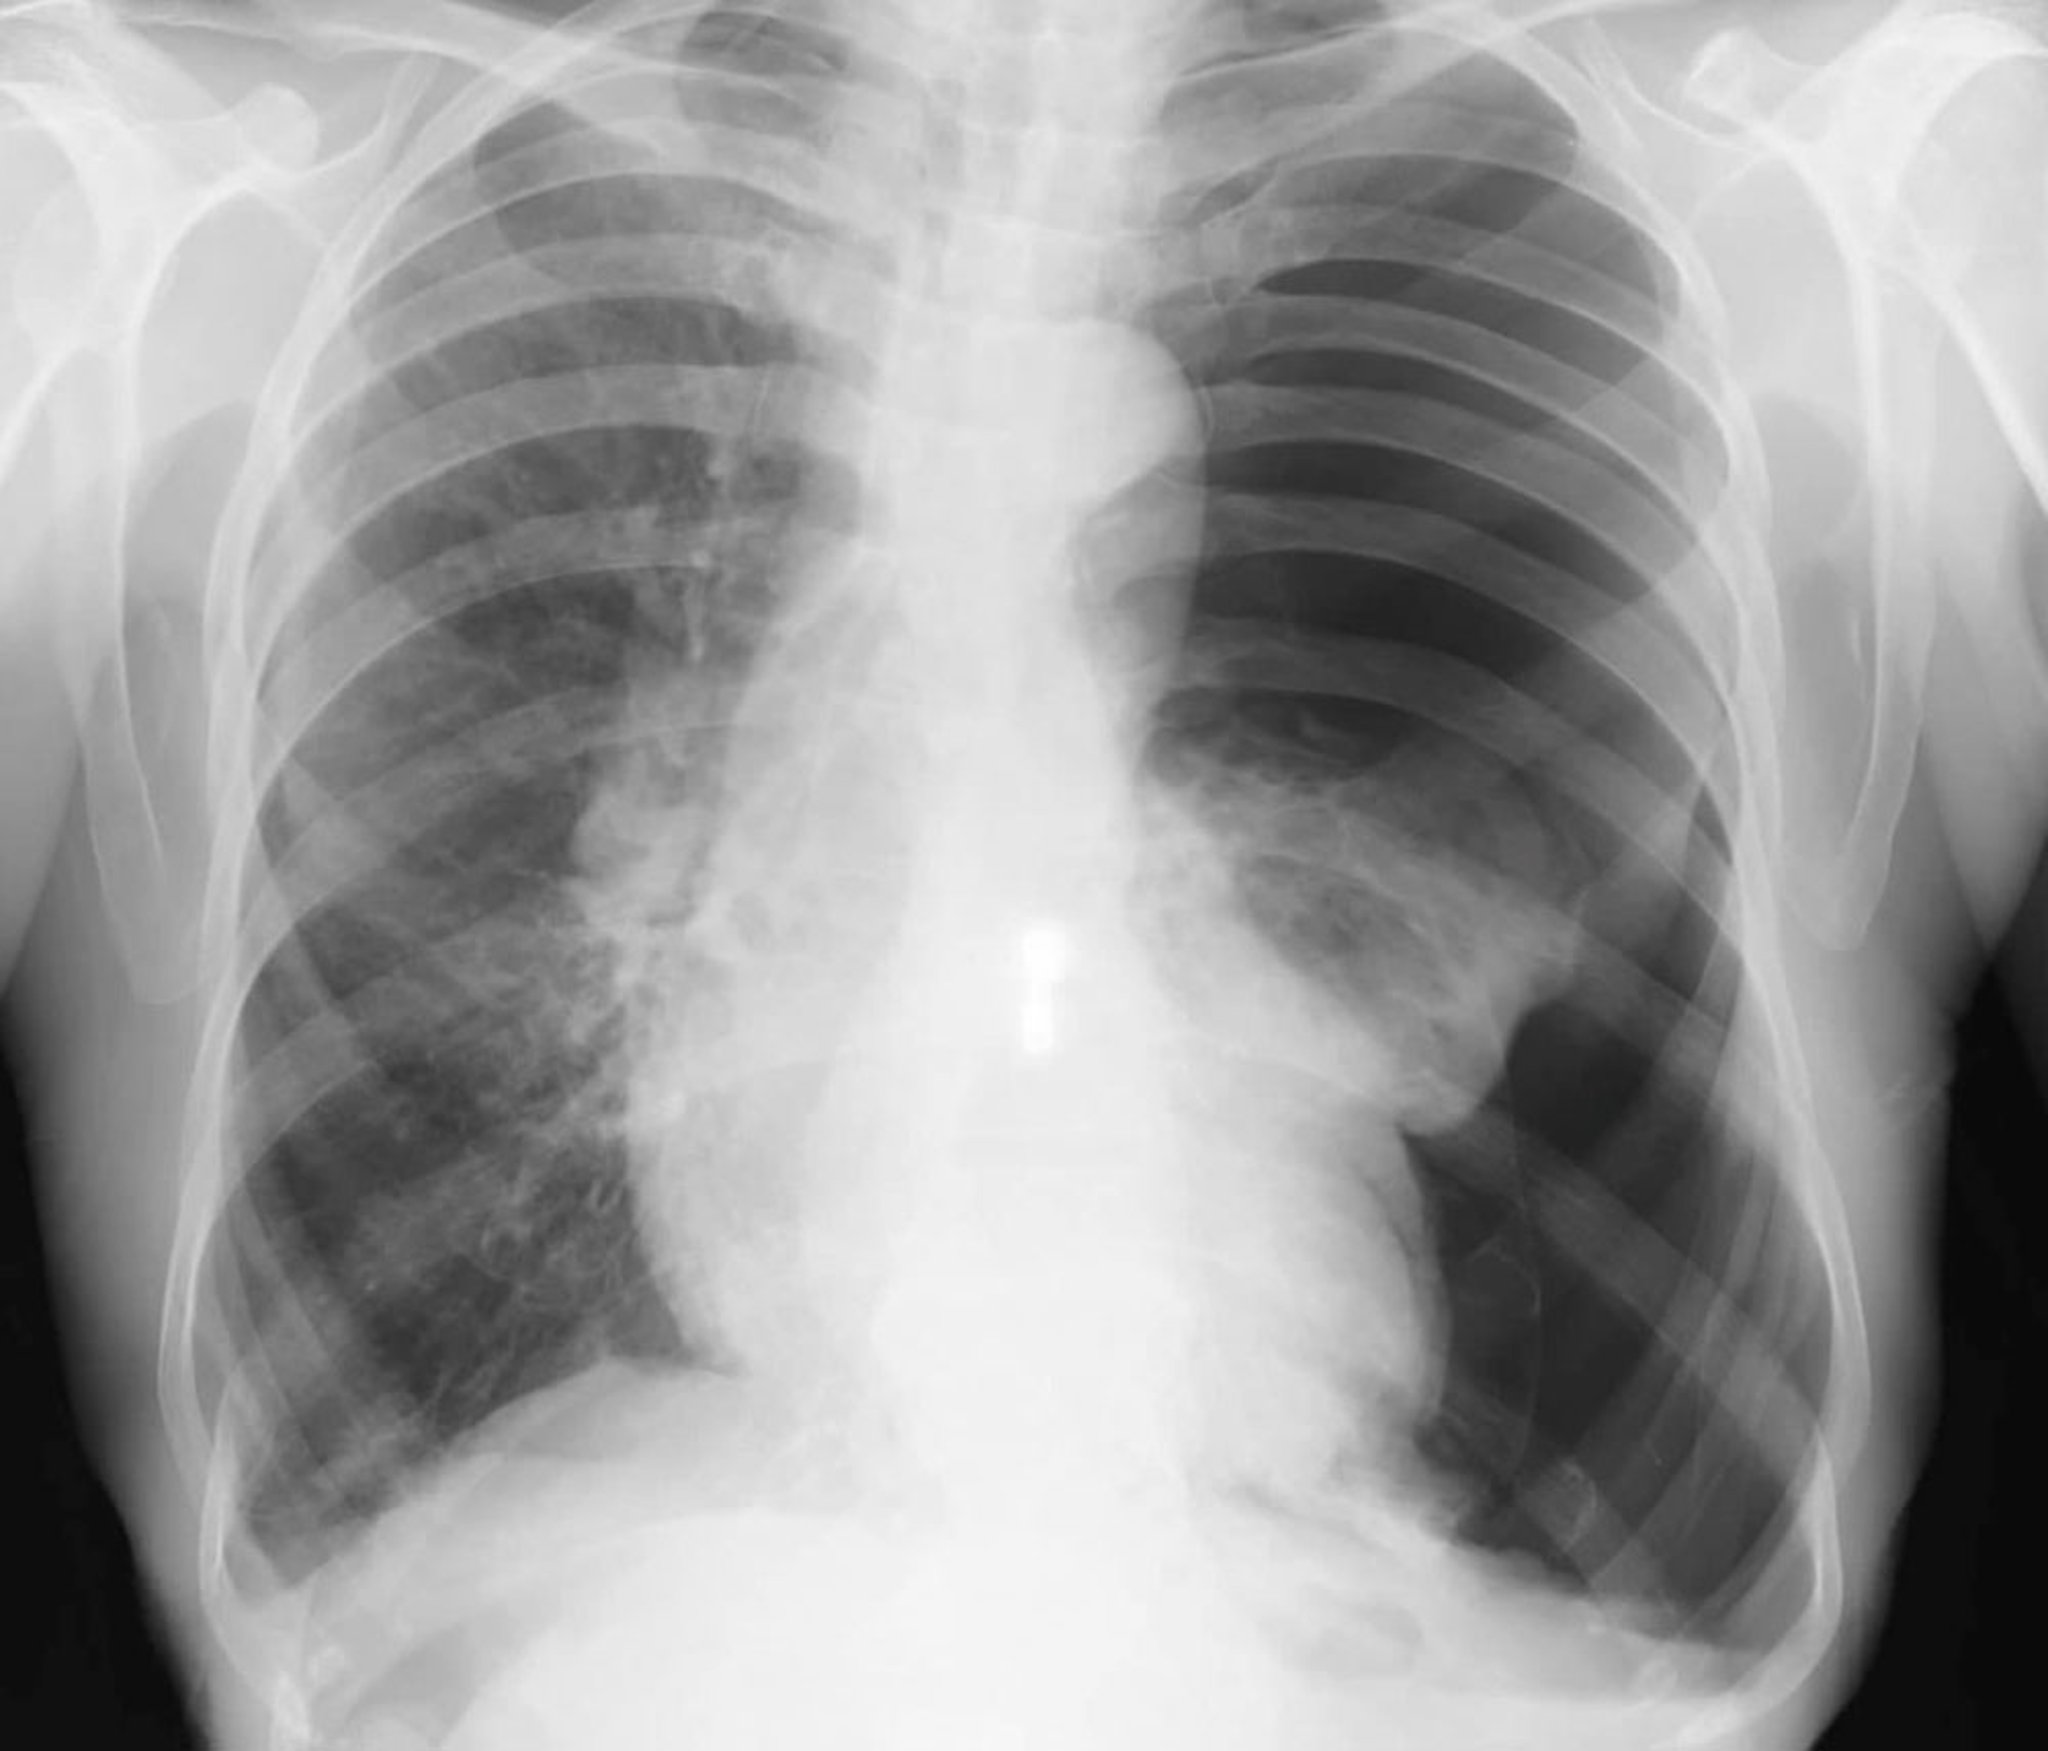

Chẩn đoán này được nghi ngờ ở những bệnh nhân có tình trạng ổn định nhưng bị khó thở hoặc đau ngực kiểu màng phổi và thường được xác nhận bằng chụp X-quang ngực tư thế thẳng đứng. Mật độ mô phổi tăng lên nếu chụp phim phổi khi thở ra, do đó làm tăng sự khác biệt về độ tương phản giữa không khí trong khoang màng phổi và mô phổi liền kề (có ít không khí hơn do sự kết hợp của trạng thái thở ra và bất kỳ tình trạng xẹp phổi nào). Viền khí không cản quang và không có vân phổi giữa phổi hoặc thùy phổi với màng phổi lá thành là dấu hiệu củan tràn khí màng phổi. Di lệch khí quản và dịch chuyển trung thất được quan sát thấy trong tràn khí màng phổi nhiều. Chẩn đoán cũng có thể được đưa ra bằng siêu âm tại giường nếu bệnh nền ở phổi không ngăn cản việc quan sát đầy đủ.

Tràn khí màng phổi ít (ví dụ: < 10%) đôi khi bị bỏ qua trên phim chụp X-quang ngực. Ở những bệnh nhân có khả năng bị tràn khí màng phổi, cần theo dõi vân phổi đến tận mép màng phổi trên phim chụp X-quang ngực. Ngay cả tràn khí màng phổi lớn cũng có thể không thấy rõ trên phim chụp X-quang tư thế nằm ngửa và cần đặc biệt chú ý đến dấu hiệu rãnh sâu (góc sườn hoành sâu bất thường) vì đây có thể là dấu hiệu duy nhất của tràn khí màng phổi trên phim chụp X-quang ở bệnh nhân nằm ngửa. Các tình trạng giống tràn khí màng phổi trên chẩn đoán hình ảnh bao gồm khí phế thũng, nếp gấp da, tấm trải giường gấp và chồng lên nhau của dạ dày hoặc ruột trên vùng phổi.

Chụp CT cũng cho phép hiển thị hình ảnh rõ ràng của tràn khí màng phổi và các bệnh lý liên quan ở bệnh nhân nằm ngửa.